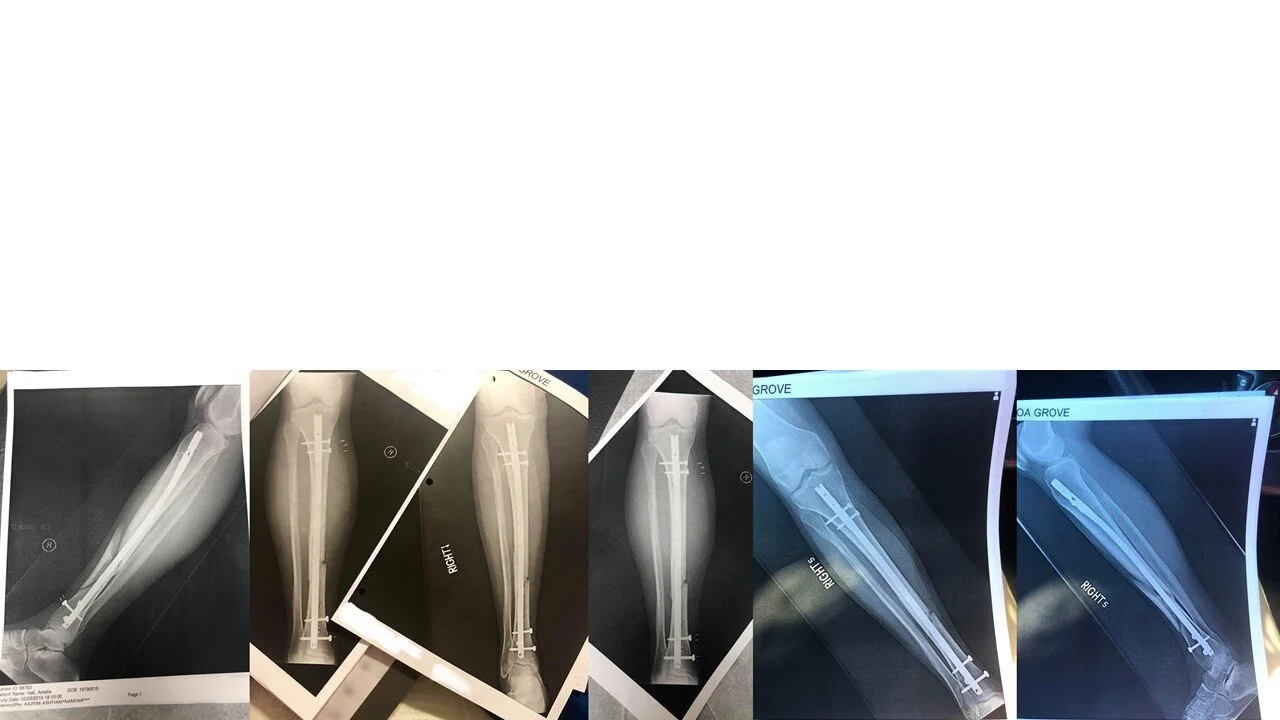

Amelia’s Recovery

hospital stay 5 days, 4 nights, beginning Feb-28, 2019

Mar-11, first visit to orthopedic doctor in Greenville. Doctor’s first order, get rid of that wrapped hospital cast, replace with high-quality ortho-boot

we used a regular rotation of ice packs, inserted into the ortho-boot, to help control pain